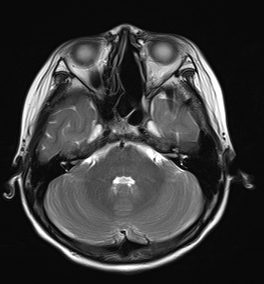

2023年底,青大附院西海岸院区儿童血液肿瘤科接诊了一名“特殊”的患儿,患儿左侧眼球突出明显,无法闭合,眼部周围组织糜烂肿胀,附有大量黄绿色分泌物,接下来的检查结果更让所有人倒吸一口凉气——影像学检查显示,患儿左侧筛窦、上颌窦、蝶窦、眼眶及鼻道内存在一巨大占位,大小约48mm×60mm×56mm的肿瘤,且已突破解剖屏障,向上侵入颅前中窝、海绵窦,向后包绕左侧颈内动脉,并严重压迫左侧视神经。病理活检最终明确为横纹肌肉瘤。

停药后影像学复查